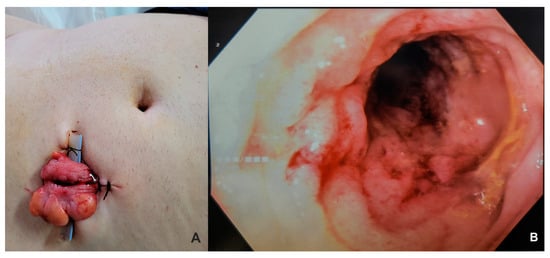

| 25 | Present Case (2025) | 64/M | UCC G3/conventional and signet ring cell | GATA3, CK 20/CK5/6, P63, CDX | colonoscopy, rectal EUS TCB | rectal tenesmus, transit disorders (constipation/small volume diarrhea), moderate dysuria | DISTAL MEDIUM R |